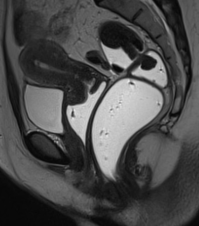

Module 5: Digestive Tract

Module coordinator : Prof. Céline Savoye-Collet

Chronic inflammatory bowel diseases – level 2- Anoperineal fistulas – level 2

- Postoperative imaging of the gastrointestinal tract, after and outside bariatric surgery – level 2

- Colonic tumors – level 2

- Post-therapeutic imaging of rectal cancer

- Anal canal cancer

- Specific features of digestive neuroendocrine tumors

- Pelvic space lesions

- Pelvic floor disorders